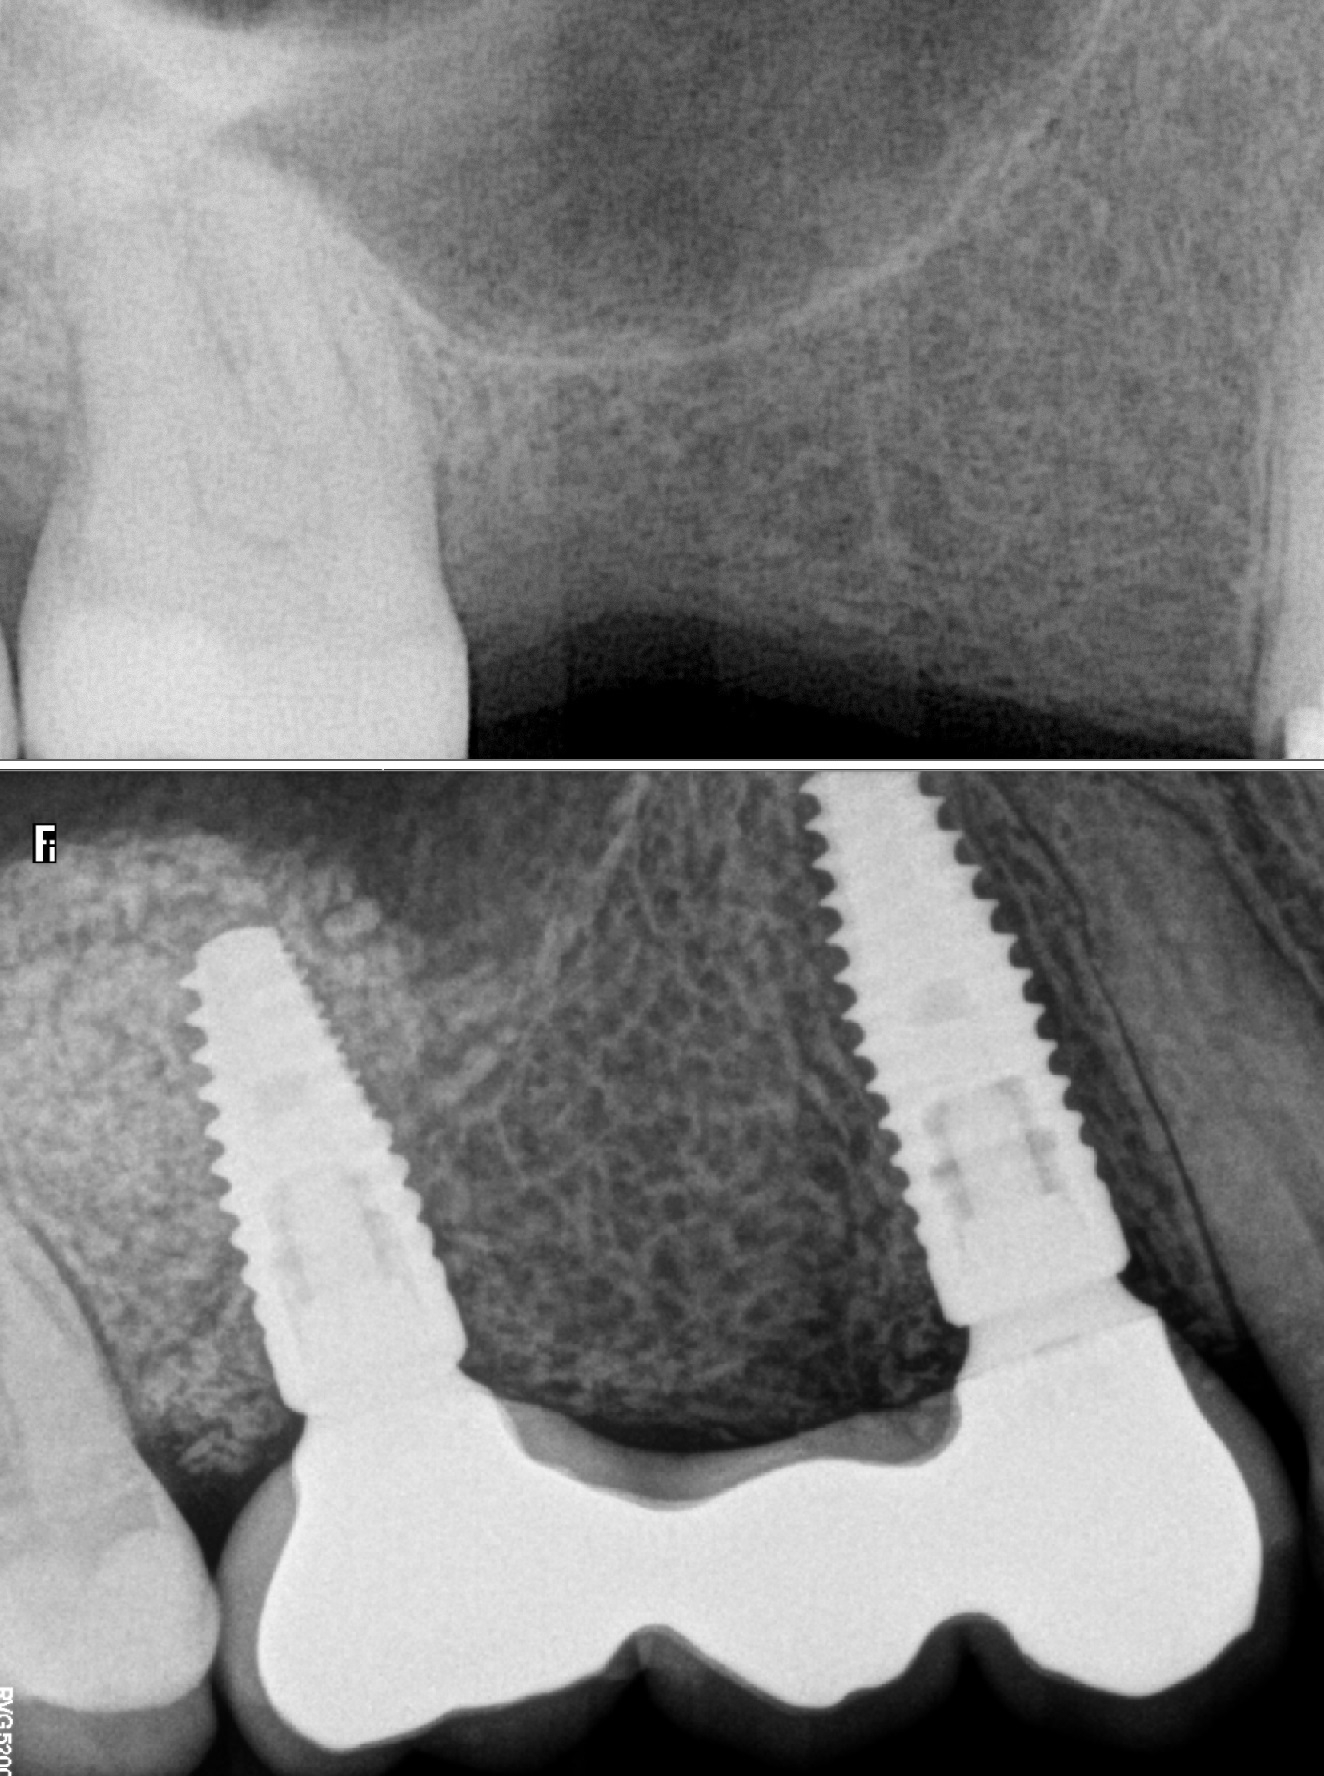

Metālkeramikas tilts + 2 zoba implanti

''Sinus lift'' un divu zobu implantu ievietošanas operācija, smaganu formētāju ievietošana

Pēc 4 mēnešiem tika izgatavots metālkeramikas tilts